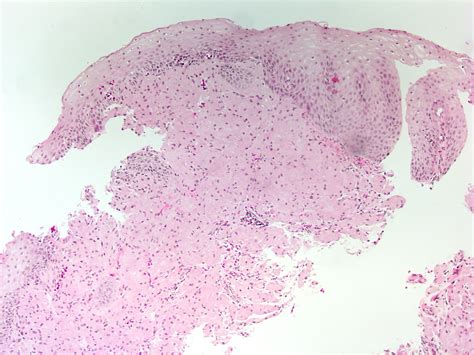

The histopathological features of granular cell tumours are distinctive and play a crucial role in their diagnosis. Key features include:

• Large, polygonal cells with abundant granular cytoplasm

• Small, centrally located nuclei

• Abundant lysosomes within the cytoplasm

• Positive staining for S-100 protein, a marker for neural and melanocytic differentiation

These features help differentiate GCTs from other types of tumours, such as rhabdomyomas and alveolar soft part sarcomas, which may have a similar appearance but different clinical behaviours.